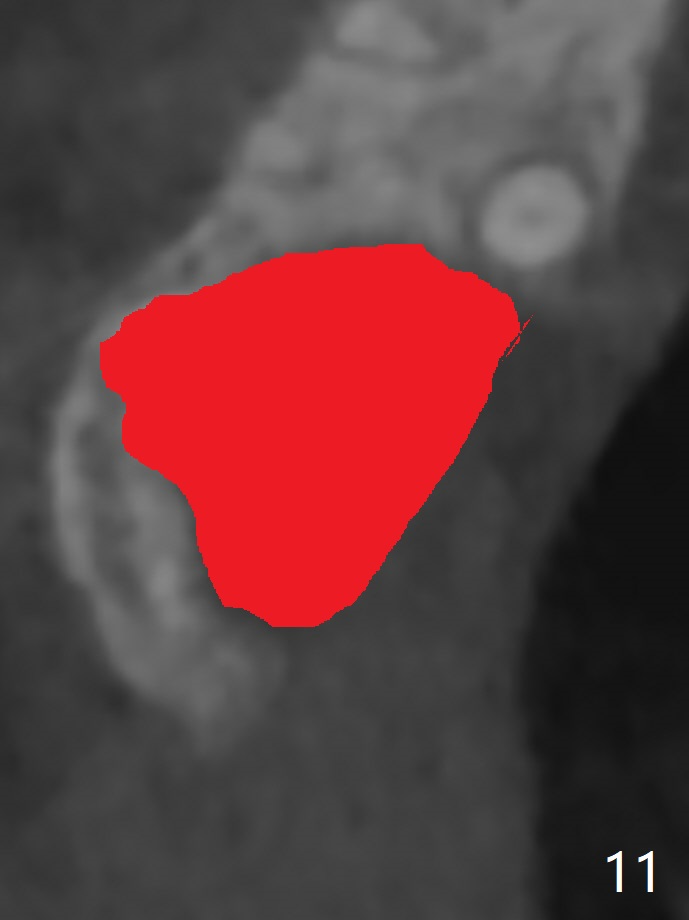

45岁女右上7严重骨质吸收终于开始出现症状(图一),虽然邻牙(6)骨质吸收也明显(图二,四,六,八,十),但是保留它,远中颊侧(DB),腭侧(P)根成为骨粉(图三,五,七,九,十一:红圆圈)支架。